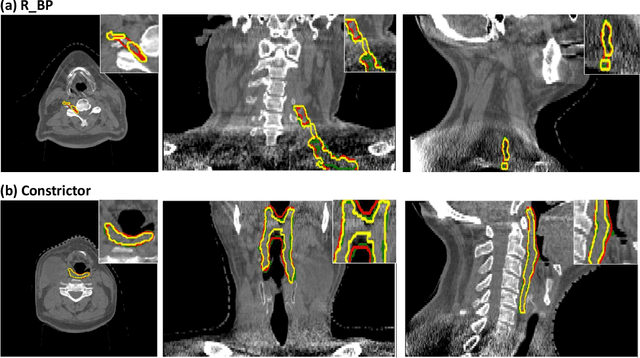

Abstract:CBCT-based online adaptive radiotherapy (ART) calls for accurate auto-segmentation models to reduce the time cost for physicians to edit contours, since the patient is immobilized on the treatment table waiting for treatment to start. However, auto-segmentation of CBCT images is a difficult task, majorly due to low image quality and lack of true labels for training a deep learning (DL) model. Meanwhile CBCT auto-segmentation in ART is a unique task compared to other segmentation problems, where manual contours on planning CT (pCT) are available. To make use of this prior knowledge, we propose to combine deformable image registration (DIR) and direct segmentation (DS) on CBCT for head and neck patients. First, we use deformed pCT contours derived from multiple DIR methods between pCT and CBCT as pseudo labels for training. Second, we use deformed pCT contours as bounding box to constrain the region of interest for DS. Meanwhile deformed pCT contours are used as pseudo labels for training, but are generated from different DIR algorithms from bounding box. Third, we fine-tune the model with bounding box on true labels. We found that DS on CBCT trained with pseudo labels and without utilizing any prior knowledge has very poor segmentation performance compared to DIR-only segmentation. However, adding deformed pCT contours as bounding box in the DS network can dramatically improve segmentation performance, comparable to DIR-only segmentation. The DS model with bounding box can be further improved by fine-tuning it with some real labels. Experiments showed that 7 out of 19 structures have at least 0.2 dice similarity coefficient increase compared to DIR-only segmentation. Utilizing deformed pCT contours as pseudo labels for training and as bounding box for shape and location feature extraction in a DS model is a good way to combine DIR and DS.